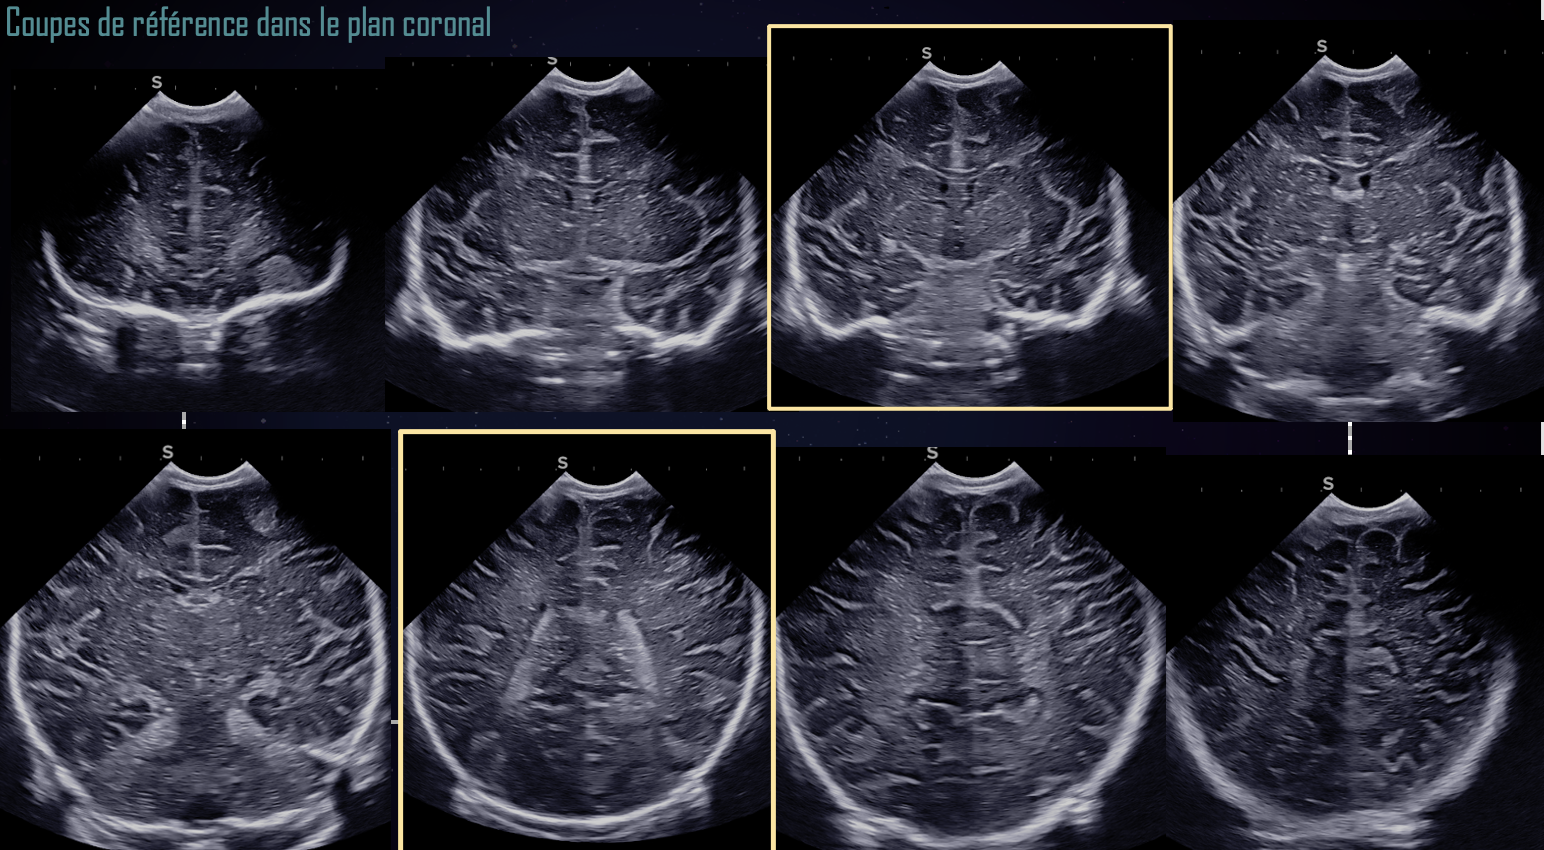

En coupes frontales, le balayage va des lobes frontaux, au-dessus des orbites, jusqu’à la limite de visibilité du parenchyme permise par la fenêtre échographique, en arrière des plexus choroïdes. Au minimum, trois coupes frontales de référence sont nécessaires : antérieure, médiane et postérieure :

* une coupe frontale antérieure passant par les cornes frontales,

* une coupe frontale médiane passant pas les trous de Monro et le 3e ventricule, permettant de mesurer le diamètre transversal des ventricules latéraux en cas de dilatation.

* Une coupe frontale postérieure passant par les plexus choroïdes.